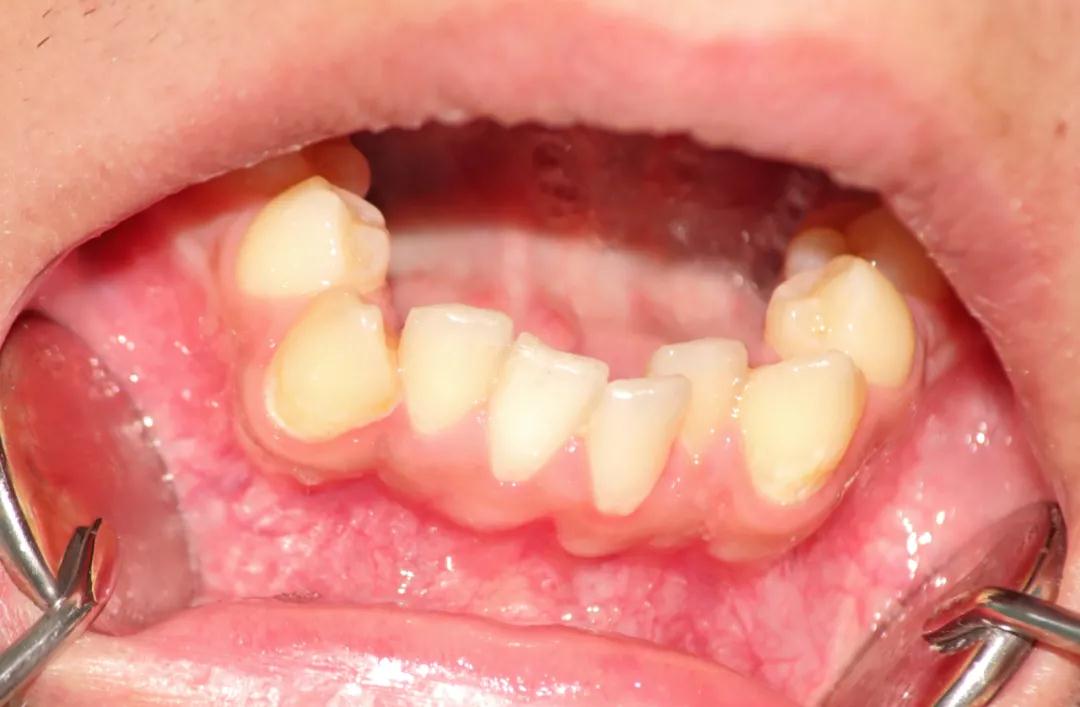

新长出来的牙是歪的怎么办?

A:这种情况通常是在上颌中切牙刚萌出的时候,会出现两个中切牙长歪了。一般分两种情况:

①切牙没有萌出的时候,可以继续观察。因为侧切牙没有萌出的时候,侧切牙的牙胚可能会向中间挤中切牙的牙根,使前切牙撇向两边,形成“八”字。

换牙期可能出现暂时性错颌,家长不用过分担心,在侧切牙萌出的时候,会推着长歪了的前切牙回到正确的位置上。

②侧切牙已经萌出,恒前切牙仍然位置不正确,就需要进行正畸治疗。

如果家长发现宝宝出现后牙长歪的情况,一定要尽早到正规医院的口腔科进行检查,拍片来判断牙齿长歪的原因,然后听取医生建议,并结合具体情况进行正畸治疗。